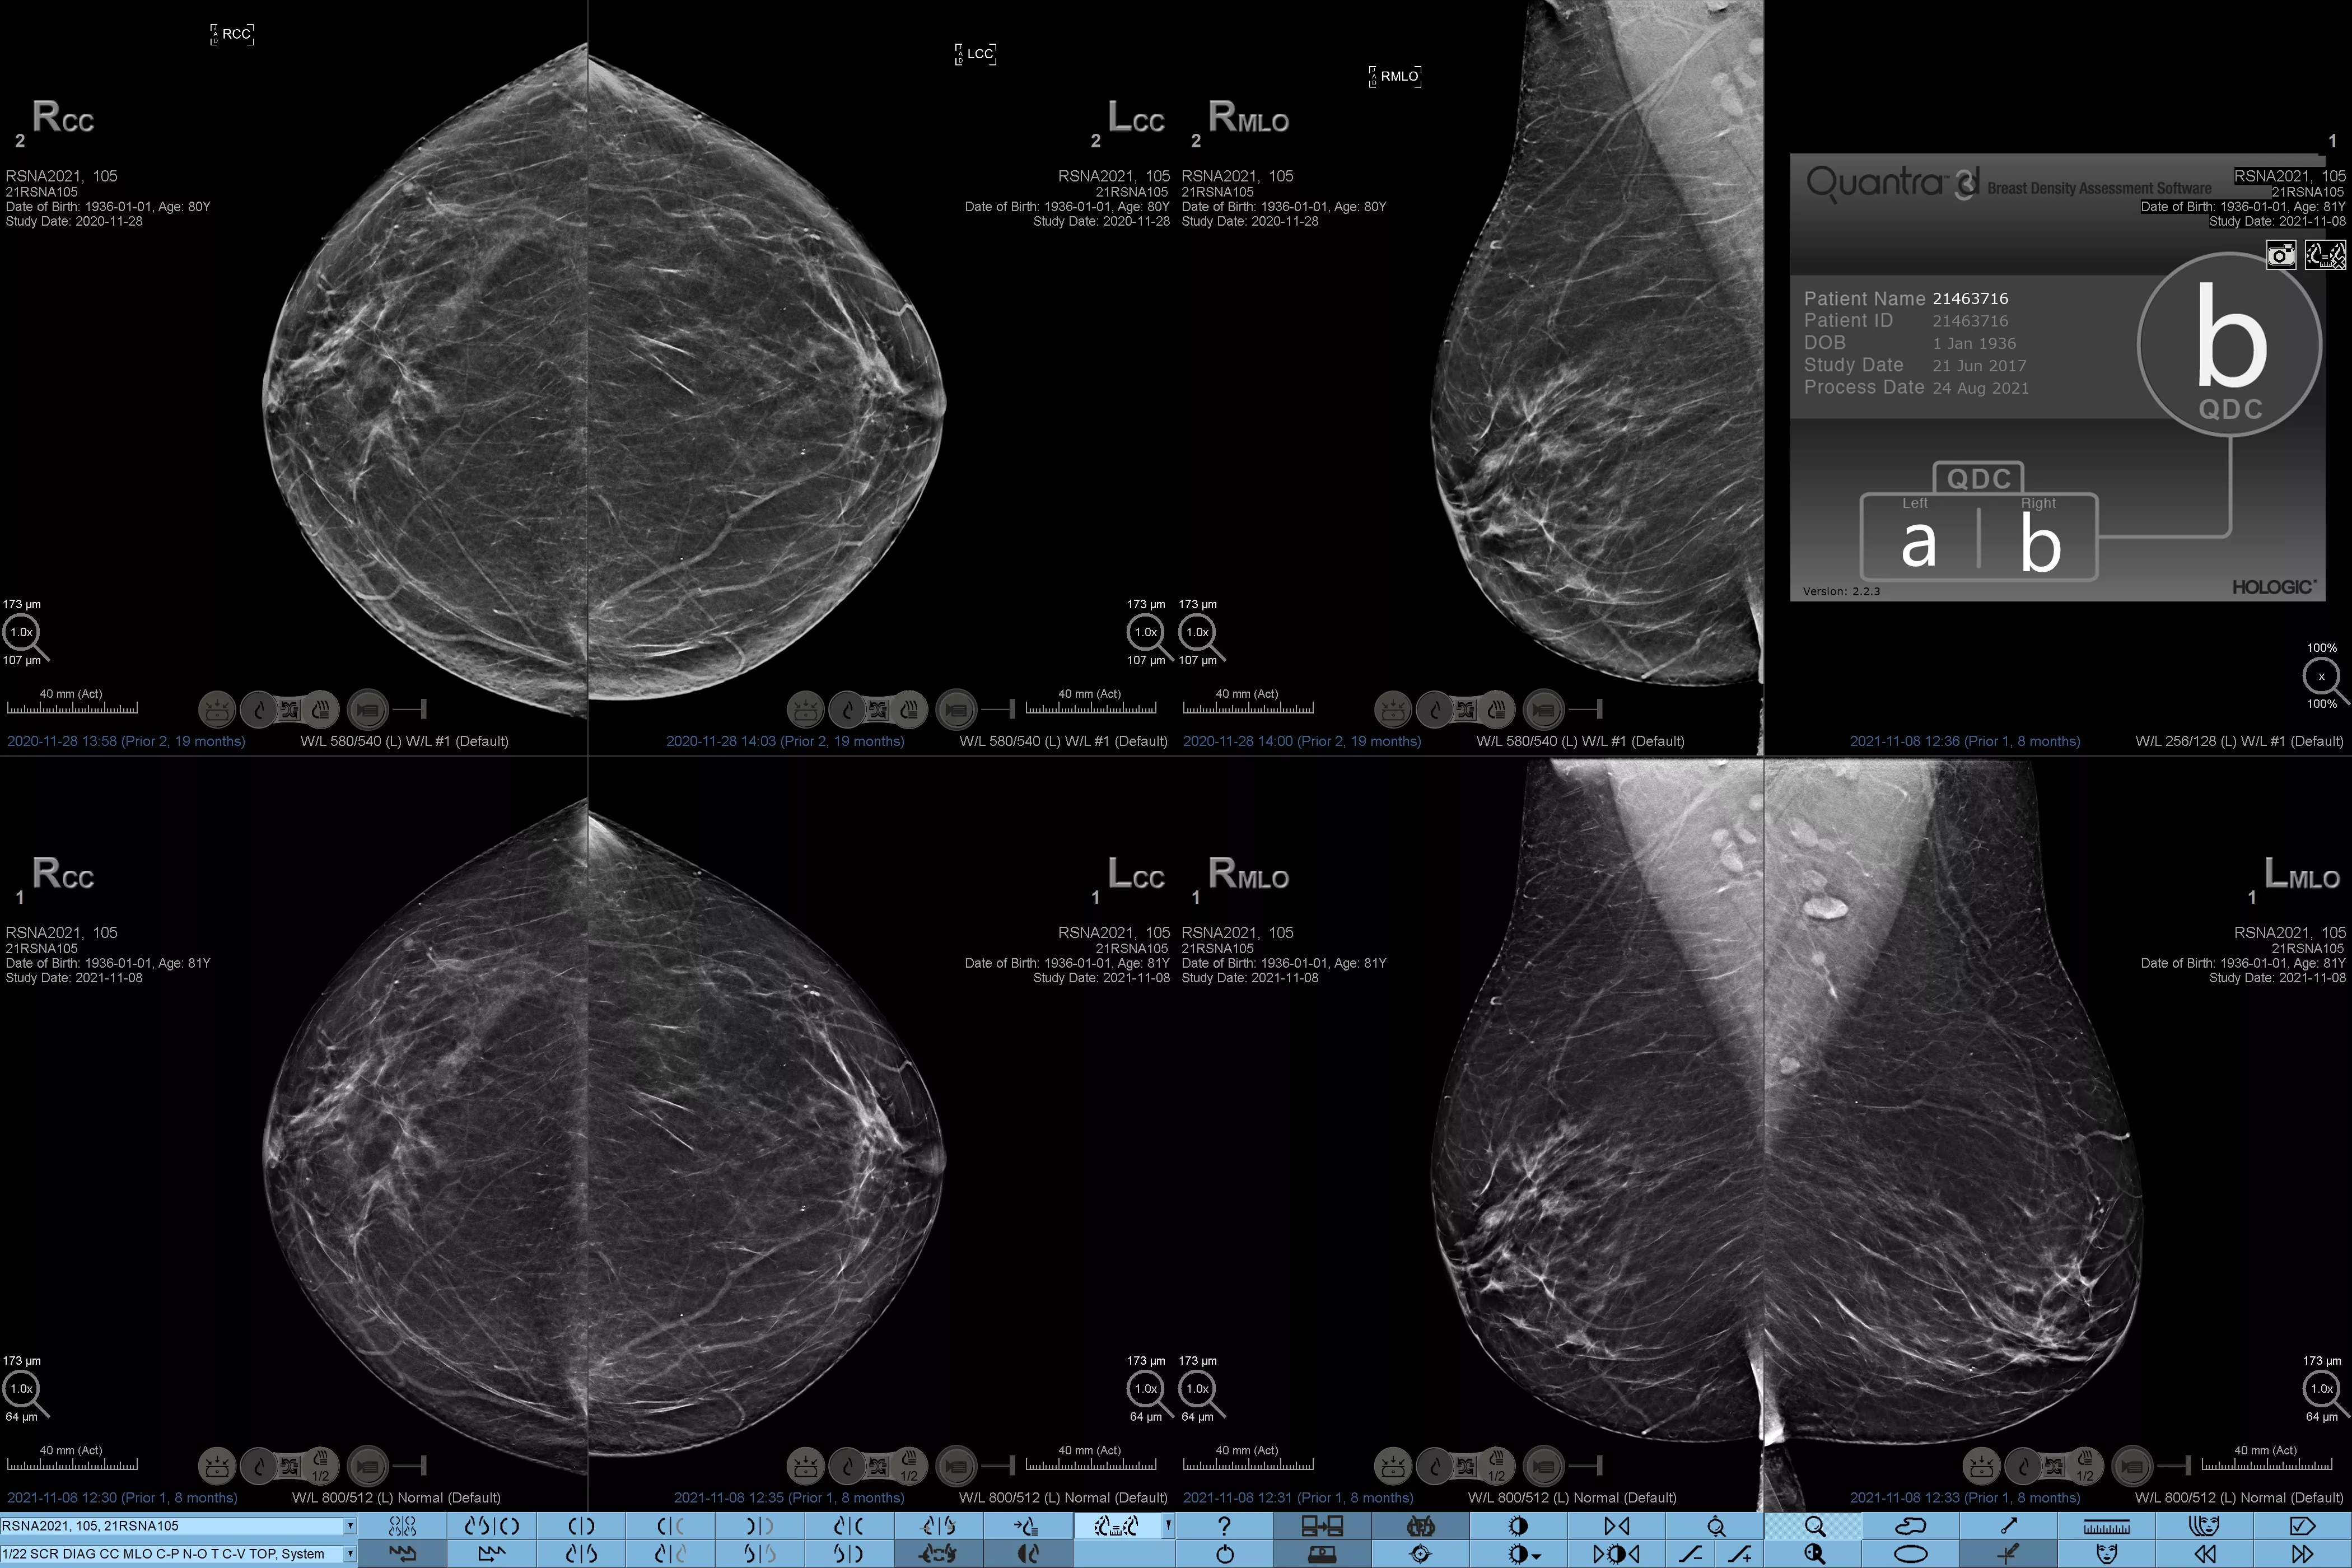

Man ved, at højere brysttæthed øger en kvindes risiko for brystkræft.1 Behovet for nøjagtige, objektive analyser er derfor afgørende. Quantra-teknologisoftwaren er drevet af maskinlæring og analyserer både 2D™ og tomosyntesebilleder for fordeling og tekstur af parenkymvæv. Den kategoriserer bryster i fire brystkompositionskategorier i overensstemmelse med vejledningen fra American College of Radiology (ACR) BI-RADS Atlas 5th Edition.2

* Scorer er baseret på ACR BI-RADS-kategorier på linje med den reviderede vejledning fra American College of Radiation (ACR) BI-RADS Atlas 5th Edition. Dette tager højde for mønster og tekstur i sammenlignet med volumen, når man bestemmer tæthed.

8. Breast composition categories as described in ACR BI-RADS Atlas.